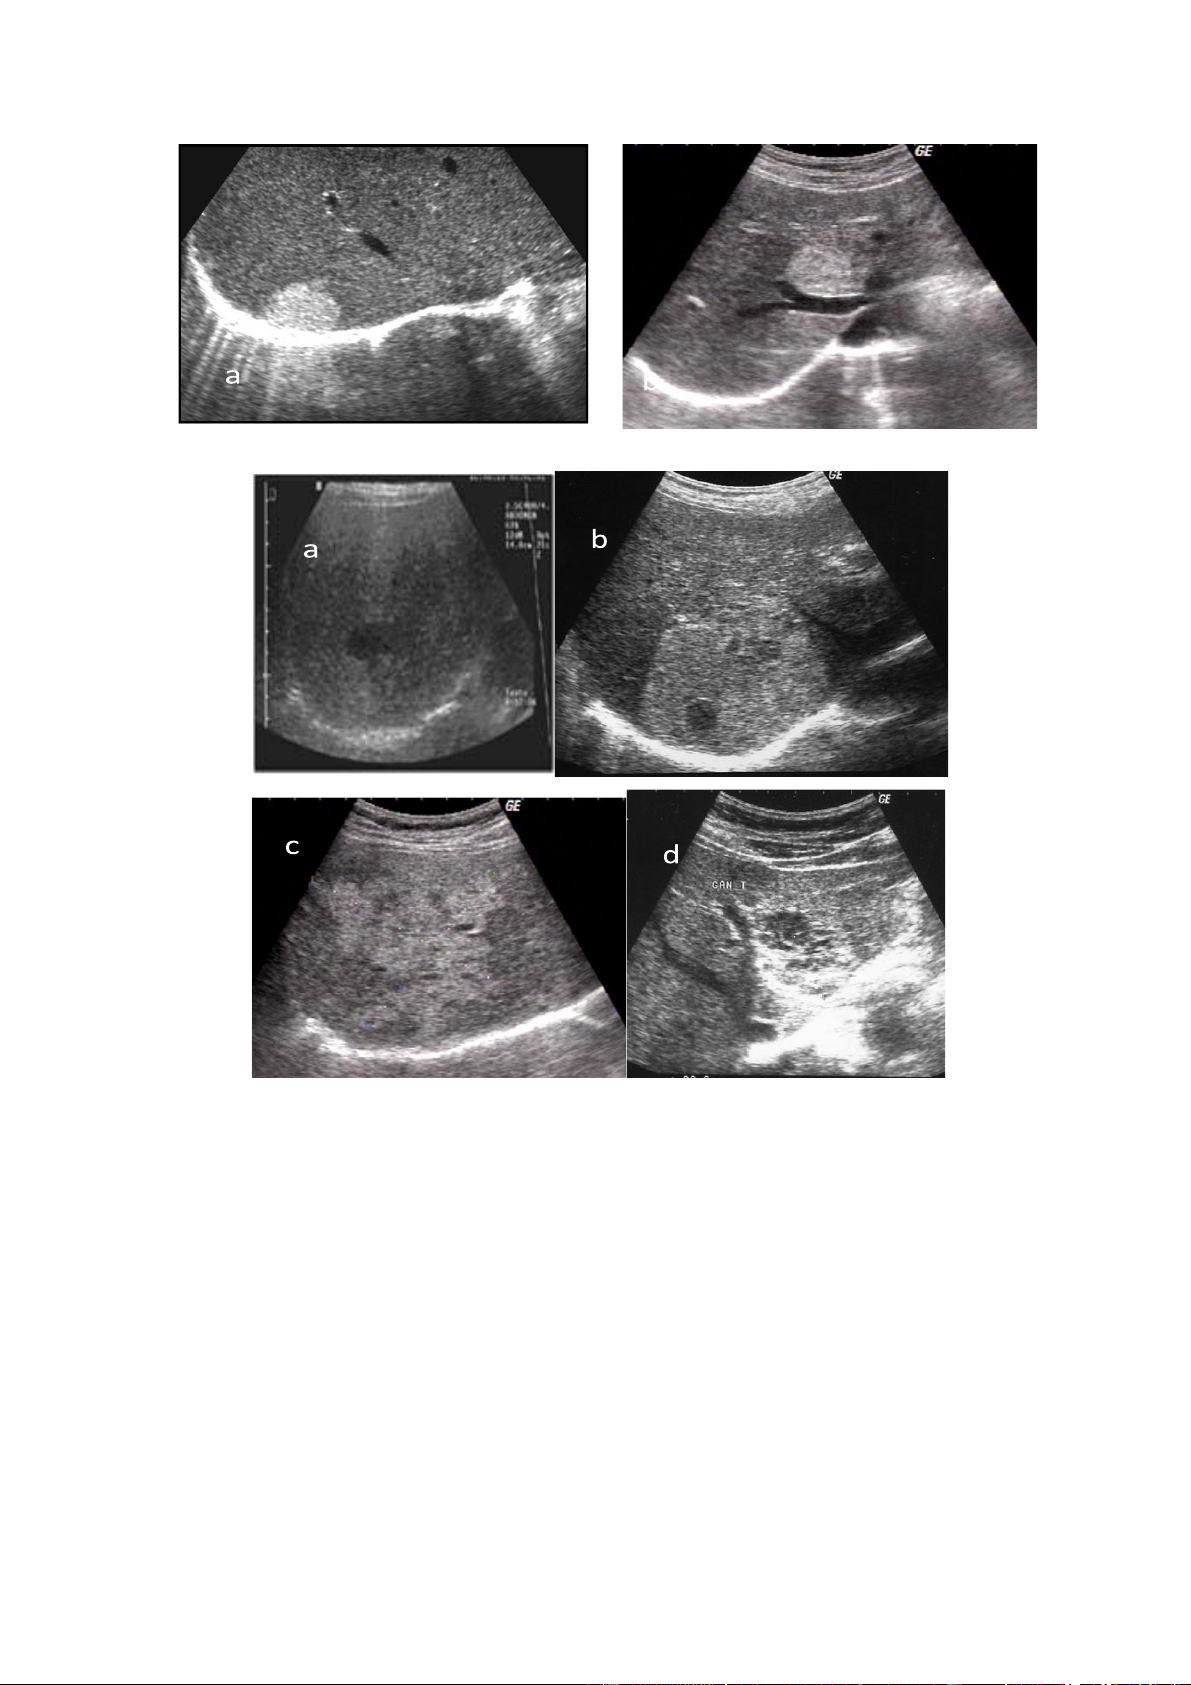

Hình. a và b. U máu điển hình

Hình. U máu không điển hình

a. U máu ít âm trên gan nhiễm mỡ

b. U máu không điển hình với những vùng giảm âm ở trung tâm

c. U máu lan toả giống như bản đồ d. U máu thể hang

Thể không điển hình

Thể không điển hình bao gồm các thể giảm âm, đồng âm và âm không đều.

U máu gan có thể giảm âm so với nhu mô gan xung quanh trong trường hợp gan

nhiễm mỡ nhiều. Cấu trúc âm không đều thường thấy ở những u gan có kích thước

lớn. Nó biểu hiện bằng một tổn thương có vùng ngoại vi tăng âm dạng u máu điển

hình và vùng trung tâm giảm hoặc rỗng âm. Cấu trúc này tương ứng với các tổn

thương xơ hoá, huyết khối, hoặc chảy máu trong khối u, đôi khi có thể có vôi hoá

trong khối. U máu thể đồng âm thường rất hiếm và dễ bỏ sót trên siêu âm. U máu lOMoAR cPSD| 58490434

thể hang thường hiếm gặp hơn, biểu hiện bằng vùng tổn thương có vỏ với nhiều hồ

dịch nhỏ, thành dày tăng âm. Một số trường hợp u máu lan toả chiếm cả một thuỳ

gan hay như hình bản đồ, đôi khi khối u có hai phần một phần nằm trong gan và một

phần nhô lên khỏi bờ gan.